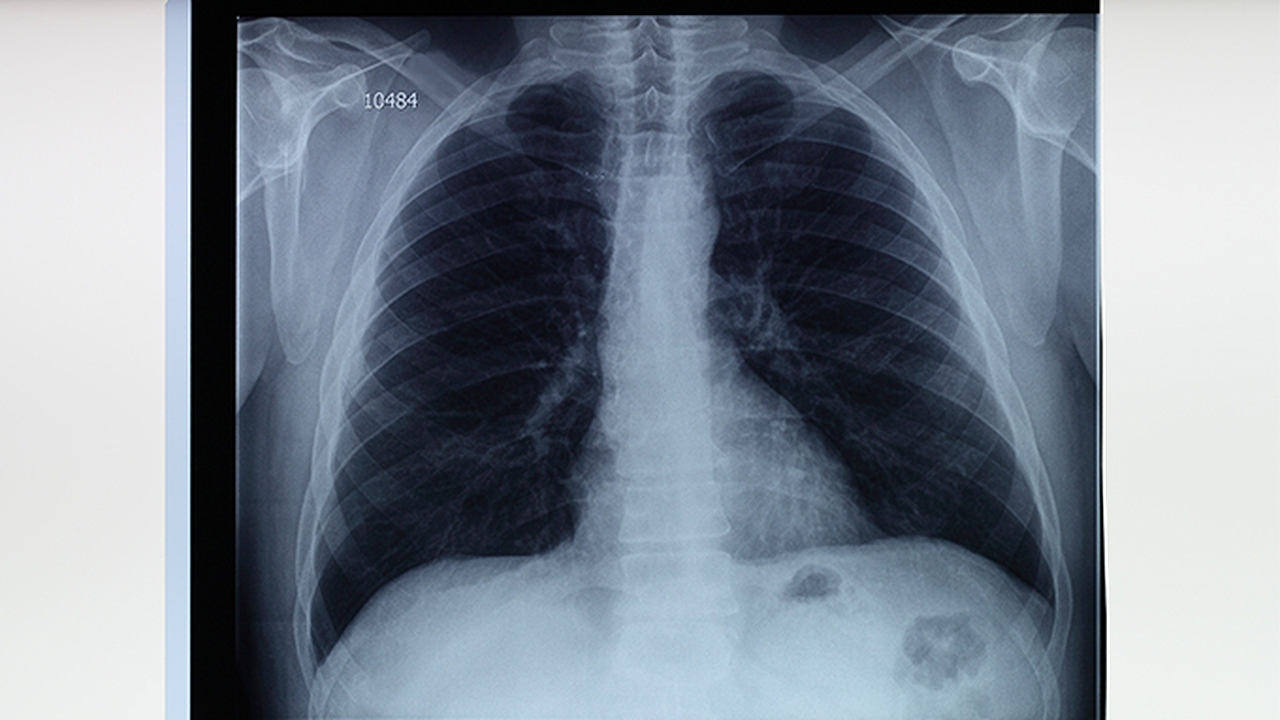

肺癌的发病原因复杂多样,包括吸烟、空气污染、职业暴露、遗传因素等。早期诊断和规范治疗对提高患者生存率至关重要。南京地区的这些医院在肺癌诊疗方面各有特色,能够满足不同患者的需求。